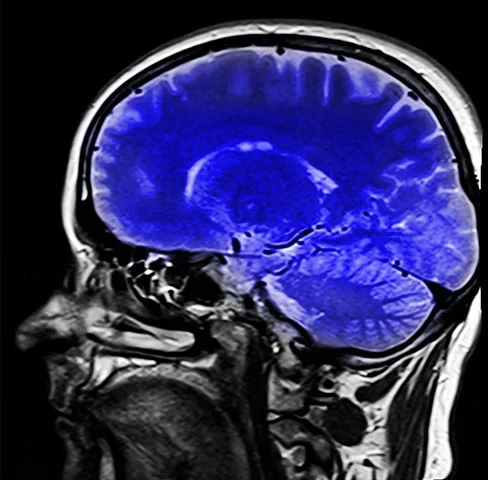

Já ouviu falar em colina? Nutriente pouco conhecido é vital para o cérebro